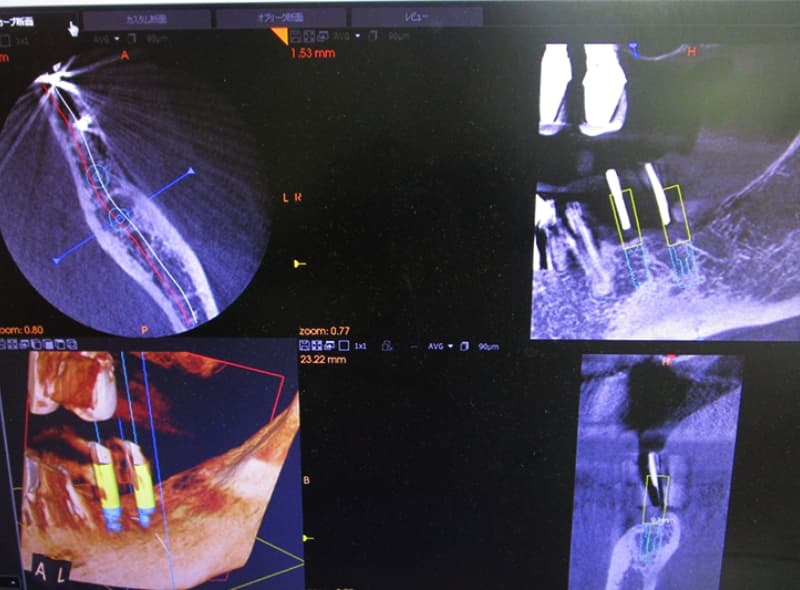

歯科用CTなどの導入

インプラント治療では、事前の検査によって顎の骨の状態を詳しく調べ、その結果を元に精密な診断および治療計画の立案を行うことが大切です。そこで当院では、表から見えない部分の状態を立体画像で取得できる歯科用CT(トロフィー社)を導入し、精密な診断に役立てています。

サージカルガイドによる

安心安全な治療

より安全で、精度の高いインプラント治療を実現するのが「サージカルガイド」を用いた手術(ガイデッドサージェリー)です。

これは、CTによる3Dシミュレーションで決定した、インプラントの理想的な埋入ポジションを寸分違わず再現するための手術支援ツールです。手術当日は、このガイドがお口の中でインプラントを入れるべき場所へと正確にナビゲートしてくれます。これにより、人為的なミスを防ぐだけでなく、歯ぐきの切開や骨を削る量を最小限に抑え、患者様のご負担を軽減することにも繋がります。